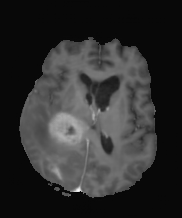

| non-CE T1w (Input) | Residual U-Net (PM) | RF Baseline | PMRF (ours) | CE T1w (GT) |

We qualitatively evaluate the top-performing Residual U-Net (Posterior Mean), RF baseline, and PMRF models (with a patch-overlap of 32 for all and integration steps for the RF baseline as well as the PMRF model) on the held-out test set. For a set of representative cases, Figure 3 compares the non-CE T1w input, Res. U-Net (equivalent to PM), RF baseline, our two-stage PMRF, and the ground truth CE T1w image. Example 1 depicts a metastases patient, example 2 a high-grade glioma patient, and example 3 a meningioma patient. Across these test cases, the Res. U-Net output accurately localizes lesions and captures their overall enhancement intensity but appears overly smooth, and muted in rim heterogeneity and fine texture. The Stage 2 PMRF refinement consistently sharpens lesion boundaries, reinstates subtle vascular and margin details, and restores characteristic enhancement patterns, yielding synthetic images nearly indistinguishable from true post-contrast scans. However, Stage 2 can only refine what the posterior-mean predictor already suggests. If a subtle rim, micro-metastasis, or vessel enhancement is entirely suppressed in Stage 1, Stage 2 has no signal to resurrect it; its perturbations stay within a narrow neighborhood of the Stage 1 output. In contrast, the RF baseline directly predicts the CE signal from the perturbed non-CE image. However, this comes with the limitation of not predicting the CE strength faithful or missing subtle details as in examples 2 and 3.